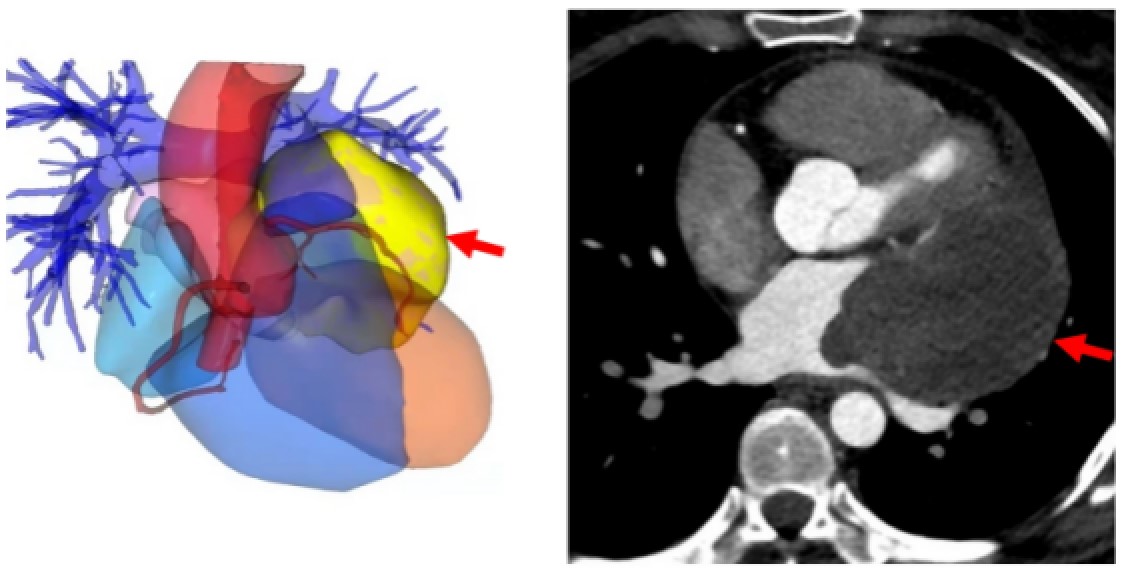

Ms. Gao, mother of three, was diagnosed with primary cardiac tumor two months ago. Whilst her oldest child is still at the age of elementary school, the news was heartbreaking for the whole family. Surgeries for cardiac tumors, angiosarcoma in particular, are ...